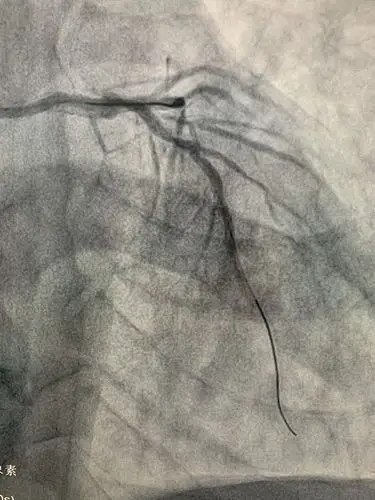

心脏支架手术是一种治疗冠状动脉疾病的手术方法,冠状动脉疾病是由于

冠状动脉支架